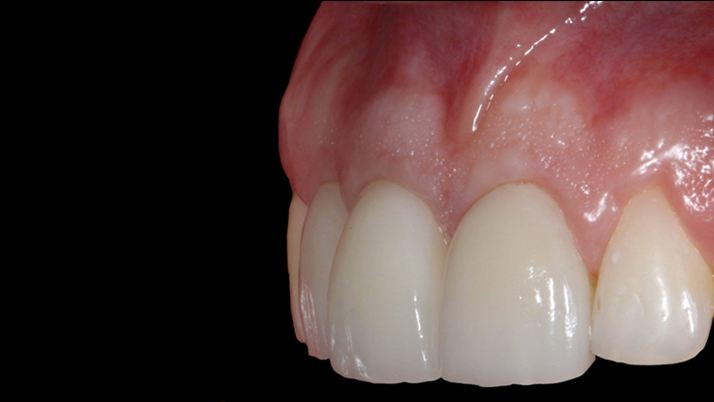

Clinical case: BPET PREDICTABILITY - State-of-the-Art SOCKET SHIELD

- Courtesy of Dr. Howard Gluckman, South Africa -

“AnyRidge is perfect for the anterior esthetic zone due to its strong initial stability & fast osseointegration.

Plus, KnifeThread® ensures space maintenance when using the PET/Socket Shield/Root Membrane Technique, showing excellent bone growth.”